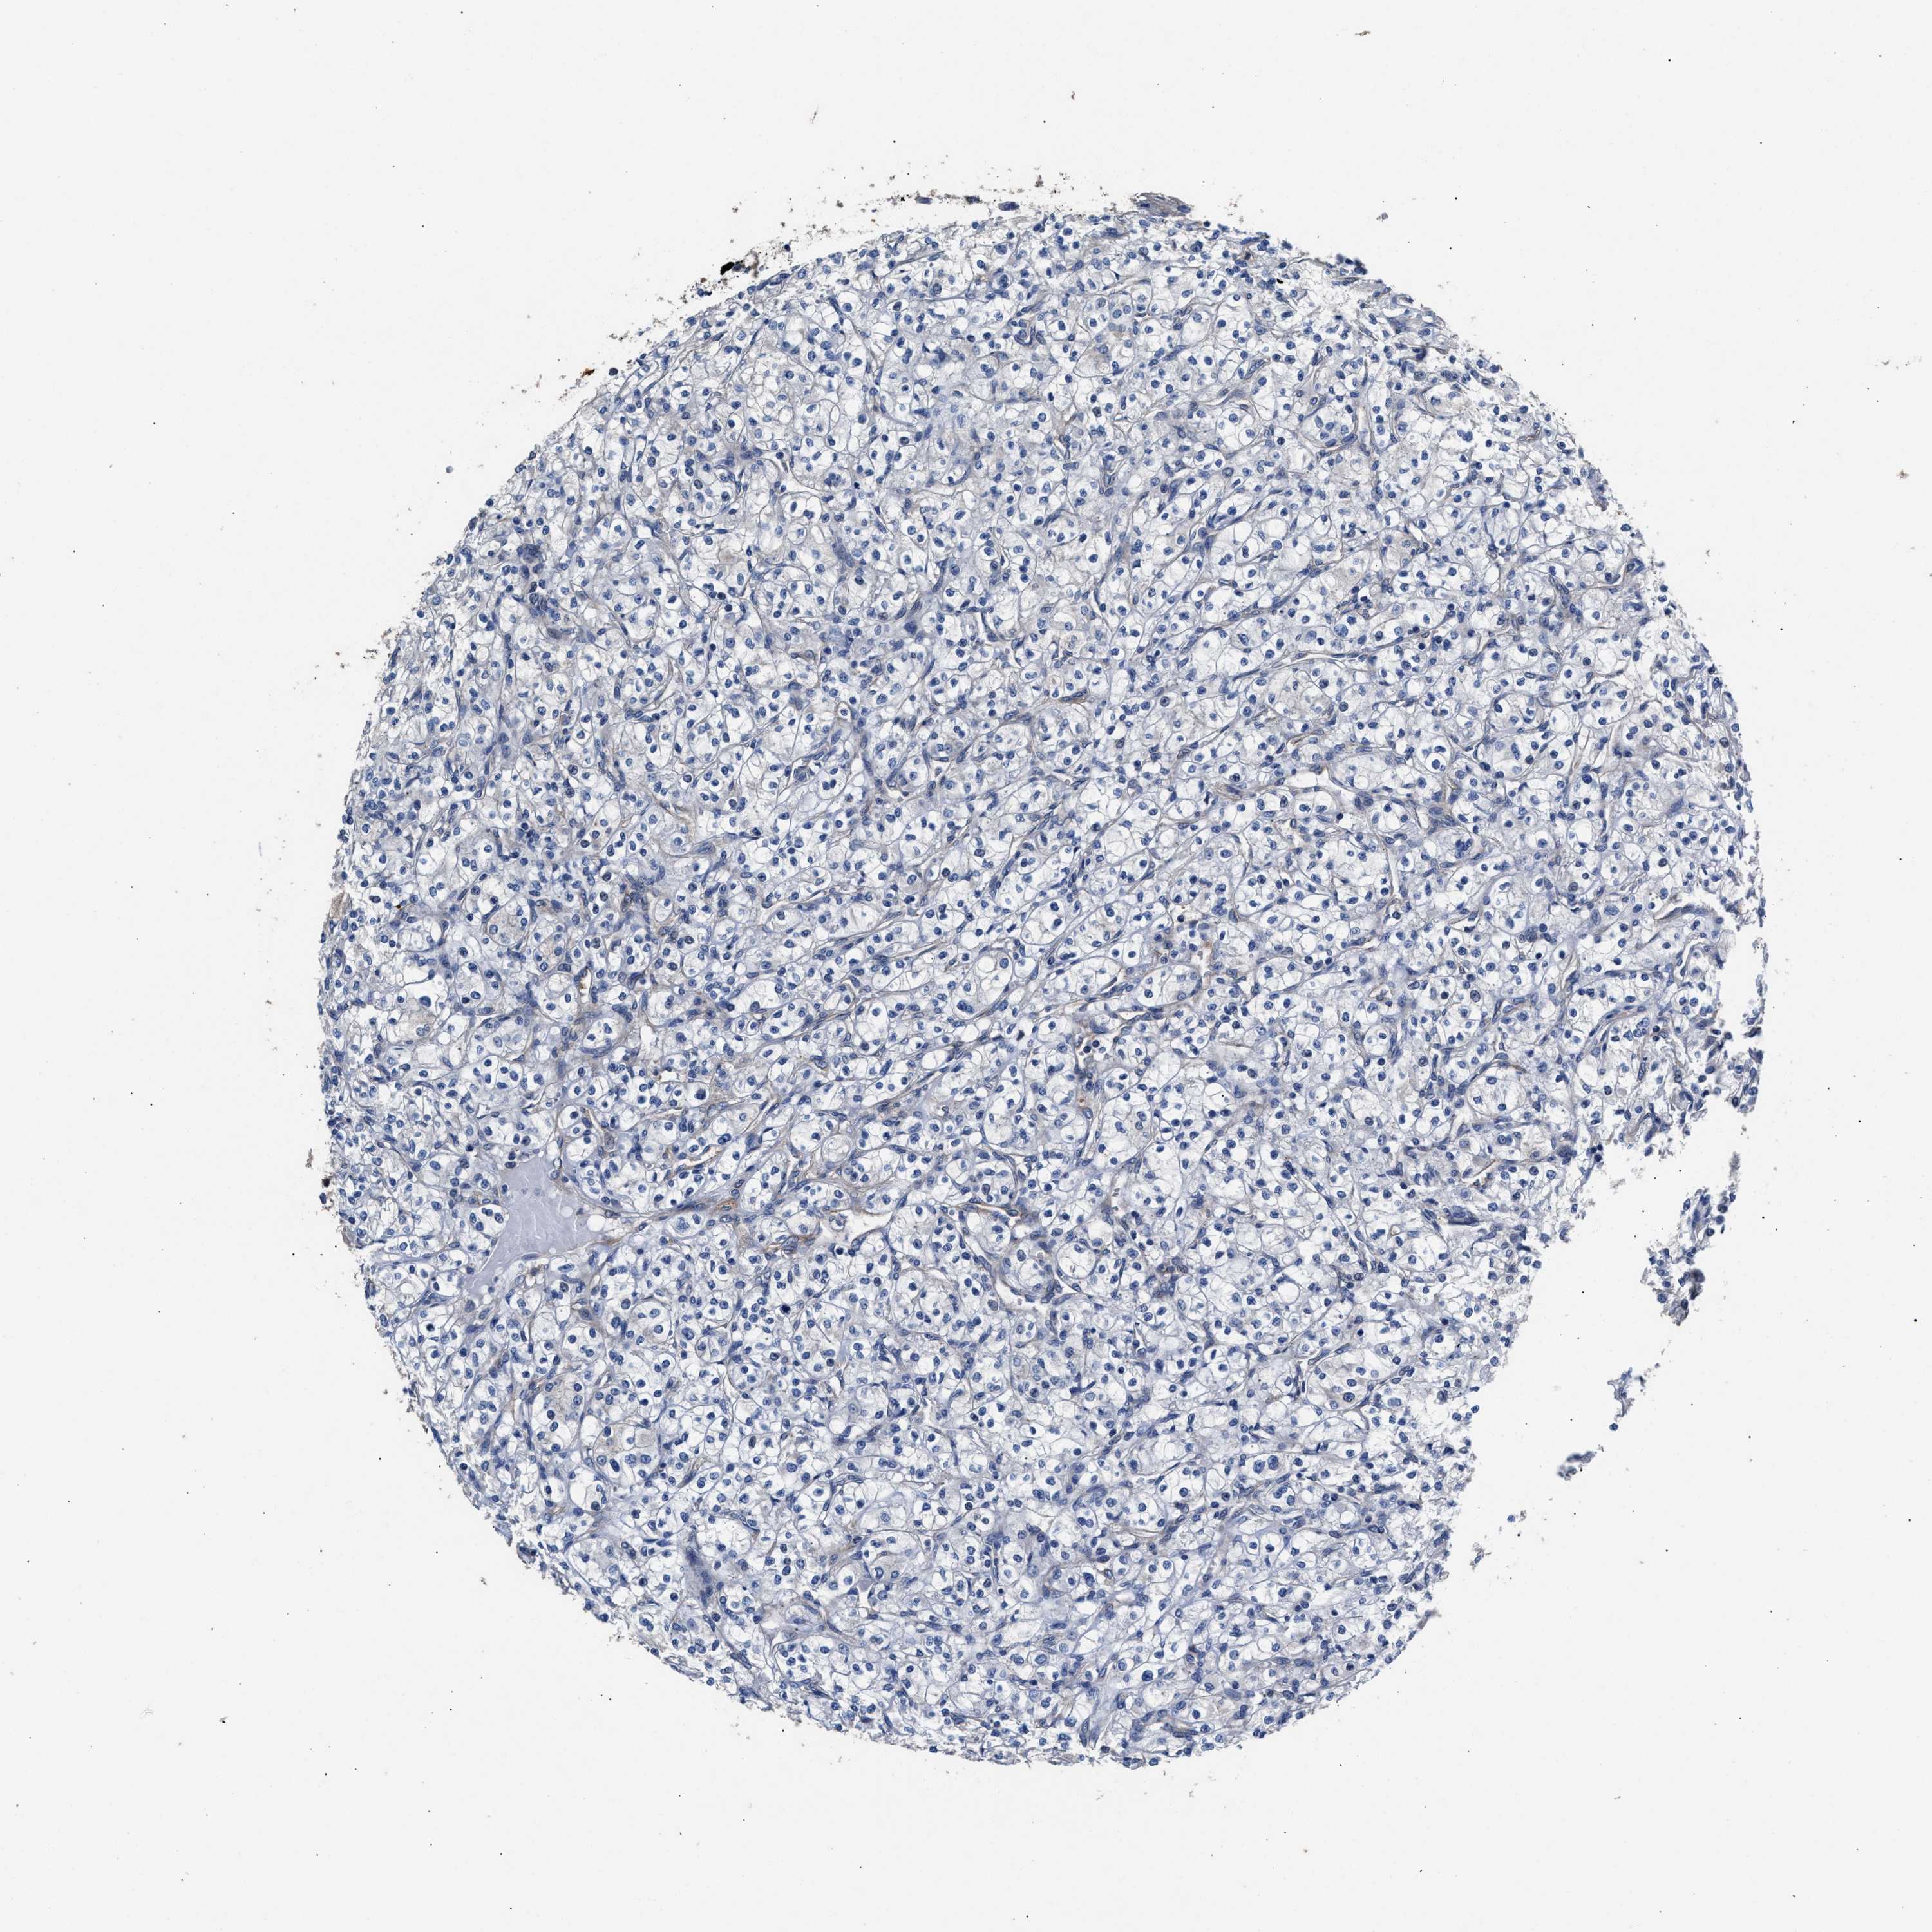

CANCER RENAL CANCER Show tissue menu

KICH TCGA KIRC TCGA KIRC VALIDATION KIRP TCGA PROTEIN RCC CPTAC PROTEIN EXPRESSION

Renal cancer

Kidney chromophobe